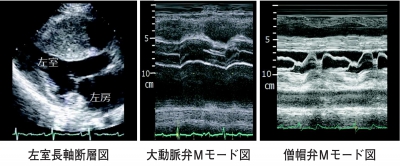

心エコー図を別に示す。認められる所見はどれか。2つ選べ。

c. 僧帽弁狭窄

d. 非対称性心室中隔肥厚

e. 僧帽弁収縮期前方運動

d 長軸像で明らかに肥厚している。

e 僧帽弁Mモードで指摘できる。